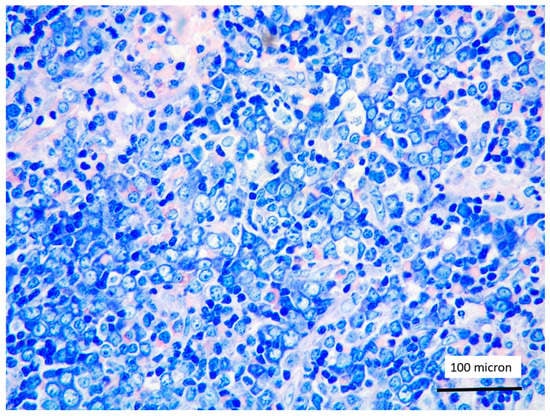

In all the cases, the lymph node histology and immunohistochemical profile were consistent with T-LBL diagnosis. The nodal architecture was effaced by a diffuse proliferation of medium-sized cells with dispersed chromatin and scarce cytoplasm (Figure 1) with high proliferative fraction and usually positive for TdT (Figure 2), CD1a and T-cell markers such as CD3 (Figure 3), CD2, CD8, CD5, CD7. B-cell markers (CD79α, CD20, PAX5 and CD22) were mostly negative; a weak CD79α co-expression was noted in 2/11 cases; myeloid (MPO, CD117, CD68KP1) and monocytic (CD68PGM1) markers were negative. In 5/11 cases, a minor component of immature myeloid cells was identified (Figure 4). Aggregates of mature eosinophils (Figure 5) admixed to the lymphoblastic proliferation were noted in 5/11 cases, whereas clusters of proerytroblasts (Figure 6 and Figure 7) were identified within T-LBL in 1/11 cases. Unexpectedly, LMO2 immunostaining was found to be negative in 9/11 T-LBLs (Figure 8); in the remaining 2 cases, LMO2 was partially expressed (less than 30% of cells) with either moderate or low degree of intensity, respectively (Figure 9).

Figure 3. CD3 positivity of T-LBL (case 5, magnification 400×).

Figure 4. Immature myeloid cells, admixed to T-LBL, highlighted by myeloperoxidase (MPO) immunostaining (case 7, magnification 200×).